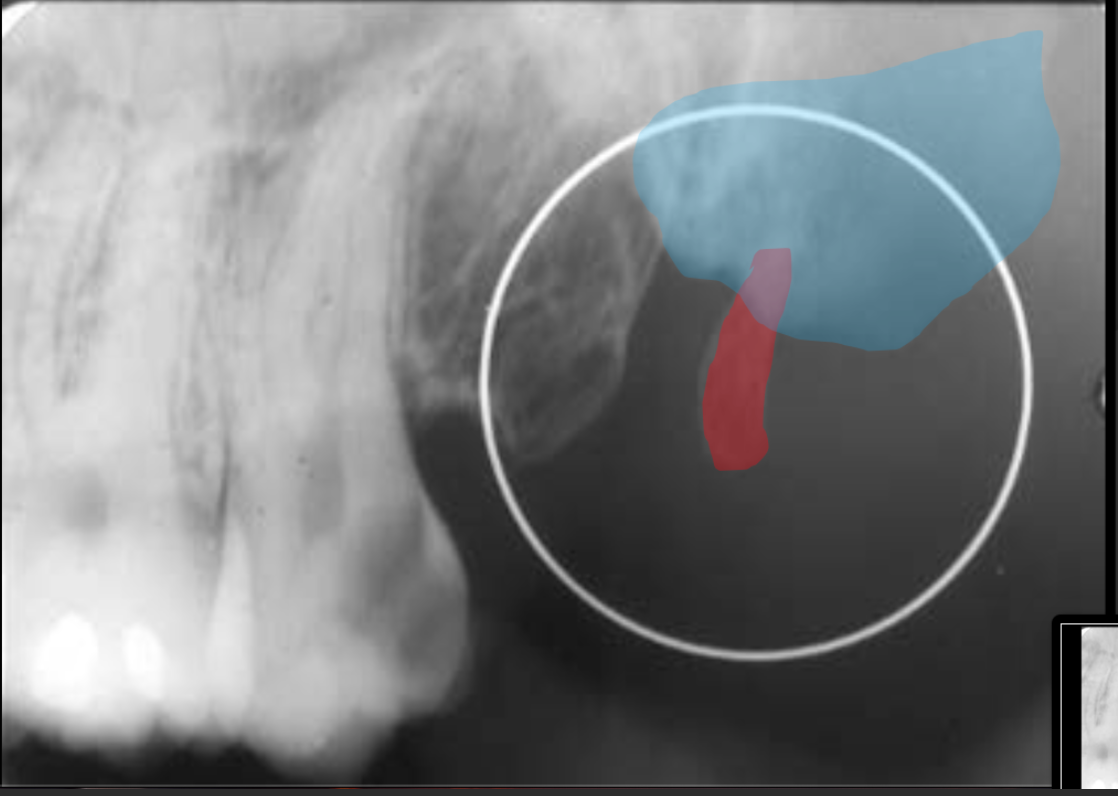

Pneumatization

A name for when the sinus recedes into the bone where a tooth is missing.

How does the maxillary sinus present in a radiograph?

It is a radiolucent space that sits above the maxillary teeth.